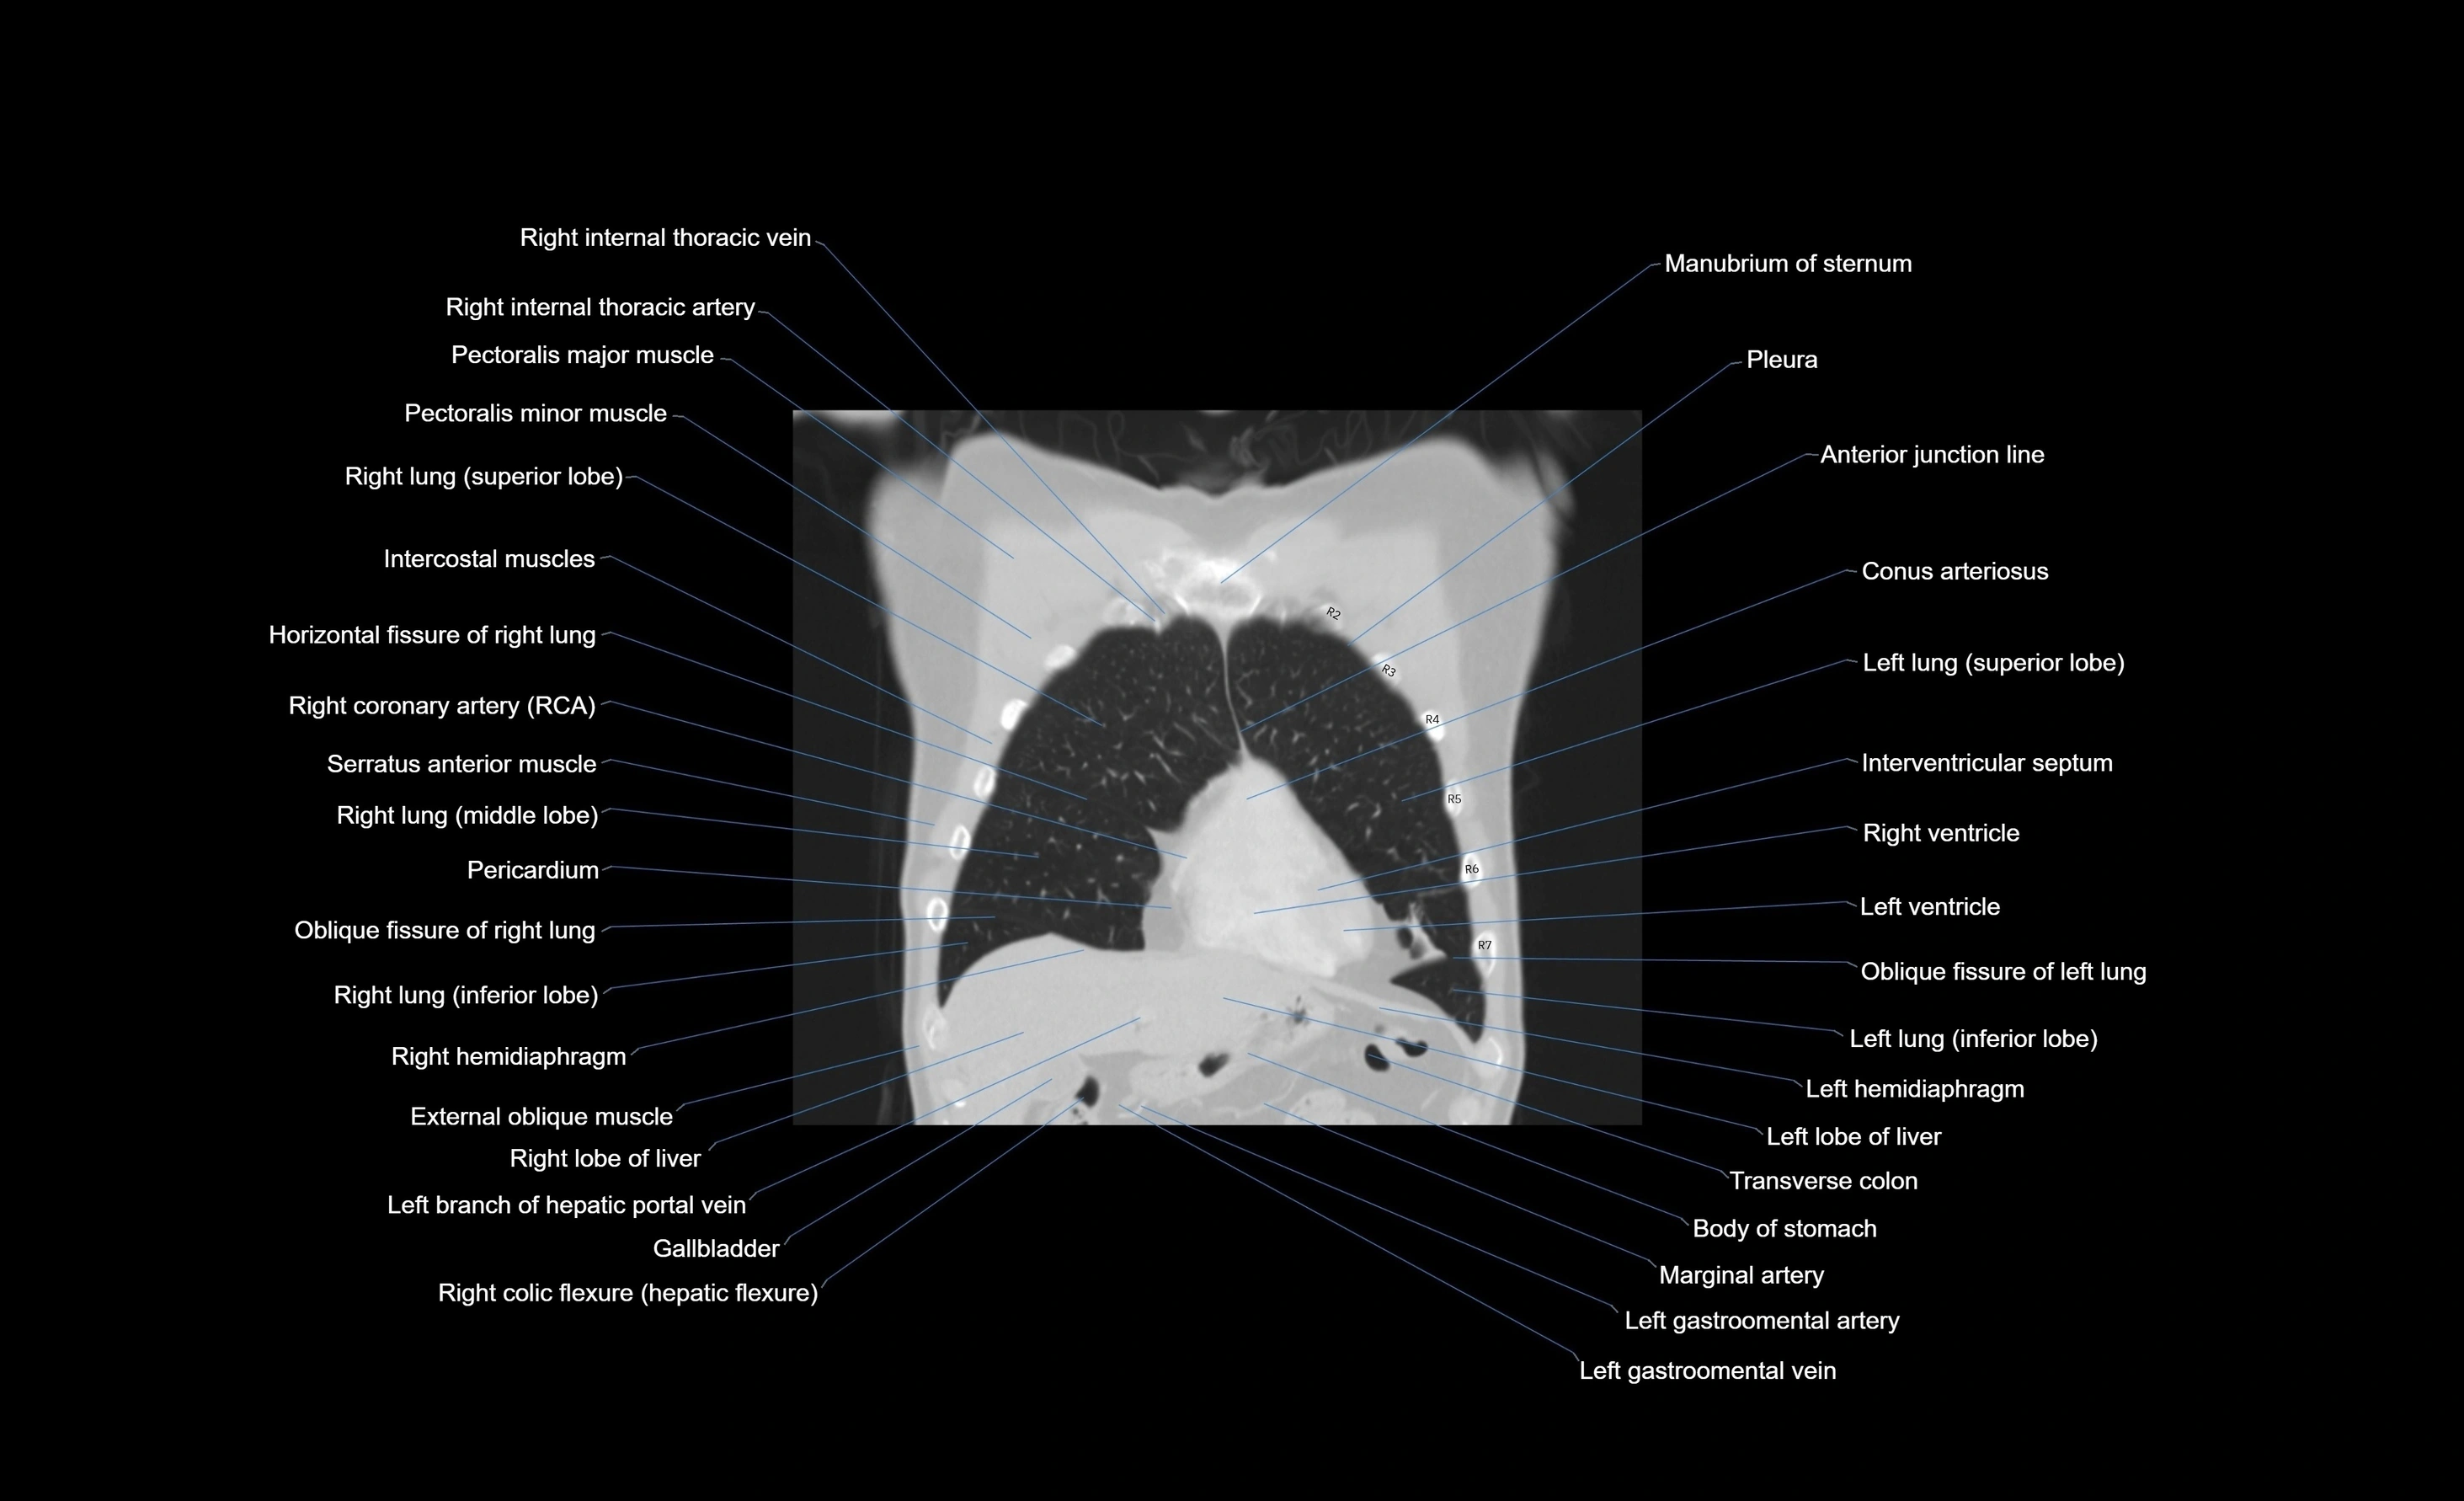

CT images